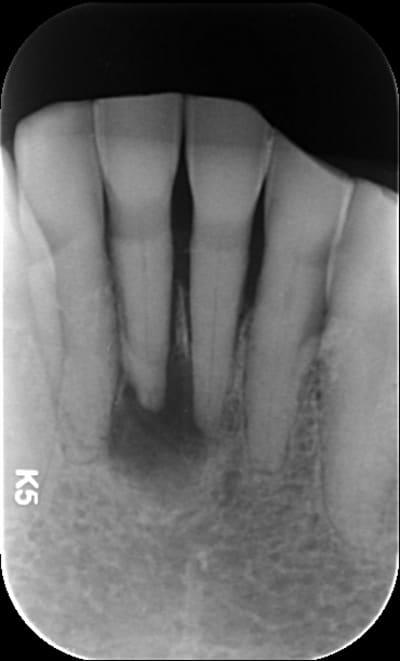

Je soigne une patiente de 88 ans, plutôt en bonne santé qui présentait une infection apicale sur 31 il y a 1 an. Voussure vestibulaire, pas vraiment douloureuse.

Bref je dévitalise, bonne irrigation et la voussure disparaît rapidement.

Je laisse cicatriser tranquillement sauf que 1 an près, c'est pire.

Ci joint le cône beam

Elle a un second canal lingual ta 31

+1 pour 2 canaux

A la base je pense qu'il y avait un second canal en lingual. Regarde les coupes horizontales tu devrais le trouver ou au moins l'imaginer. Sur les coupes sagittales, le canal que tu as obture est deporte en vestibulaire, c'est une bonne indication. Sur la retro tu vois bien les deux racines de l'incisive latérale, tu trouves en general 2 canaux sur la centrale dans ce cas la.